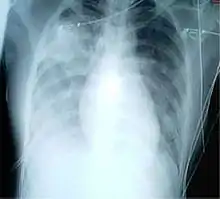

Diffuse shadowing

The differential for diffuse shadowing is very broad and can defeat even the most experienced radiologist. It is seldom possible to reach a diagnosis on the basis of the chest radiograph alone: high-resolution CT of the chest is usually required and sometimes a lung biopsy. The following features should be noted:

- type of shadowing (lines, dots or rings)

- reticular (crisscrossing lines)

- companion shadow (lines paralleling bony landmarks)

- nodular (many small dots)

- rings or cysts

- ground glass

- consolidation (diffuse opacity with air bronchograms)

- location (where is the lesion worst?)

- upper (e.g., sarcoid, tuberculosis, silicosis/pneumoconiosis, ankylosing spondylitis, Langerhans cell histiocytosis)

- lower (e.g., cryptogenic fibrosing alveolitis, connective tissue disease, asbestosis, drug reactions)

- central (e.g., pulmonary edema, alveolar proteinosis, lymphoma, Kaposi's sarcoma, PCP)

- peripheral (e.g., cryptogenic fibrosing alveolitis, connective tissue disease, chronic eosinophilic pneumonia, bronchiolitis obliterans organizing pneumonia)

- lung volume

- increased (e.g., Langerhans cell histiocytosis, lymphangioleiomyomatosis, cystic fibrosis, allergic bronchopulmonary aspergillosis)

- decreased (e.g., fibrotic lung disease, chronic sarcoidosis, chronic extrinsic allergic alveolitis)

Pleural effusions may occur with cancer, sarcoid, connective tissue diseases and lymphangioleiomyomatosis. The presence of a pleural effusion argues against pneumocystis pneumonia.

- Reticular (linear) pattern

- (sometimes called "reticulonodular" because of the appearance of nodules at the intersection of the lines, even though there are no true nodules present)

- Nodular pattern

- sarcoidosis

- silicosis/pneumoconiosis

- extrinsic allergic alveolitis

- Cystic

- cryptogenic fibrosing alveolitis (late stage "honeycomb lung")

- cystic bronchiectasis

- Langerhans cell histiocytosis

- lymphangioleiomyomatosis

- Ground glass

- Consolidation

- pneumonia

- alveolar haemorrhage

- alveolar cell carcinoma

- vasculitis